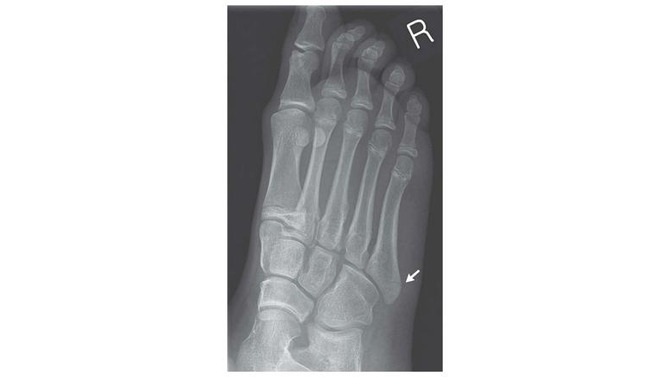

折れてしまったのは「中足骨」という足の中程にある骨。

足の指と足を繋ぐ骨で、細く弱いため比較的折れやすいことでも知られているそうです。

彼女の場合は右足の外側の中足骨の基部が折れてしまっており、松葉杖をついての通院治療が行われました。バランスが崩れた際に筋肉が激しく骨を引っ張ったことが原因ではないかと報告されています。